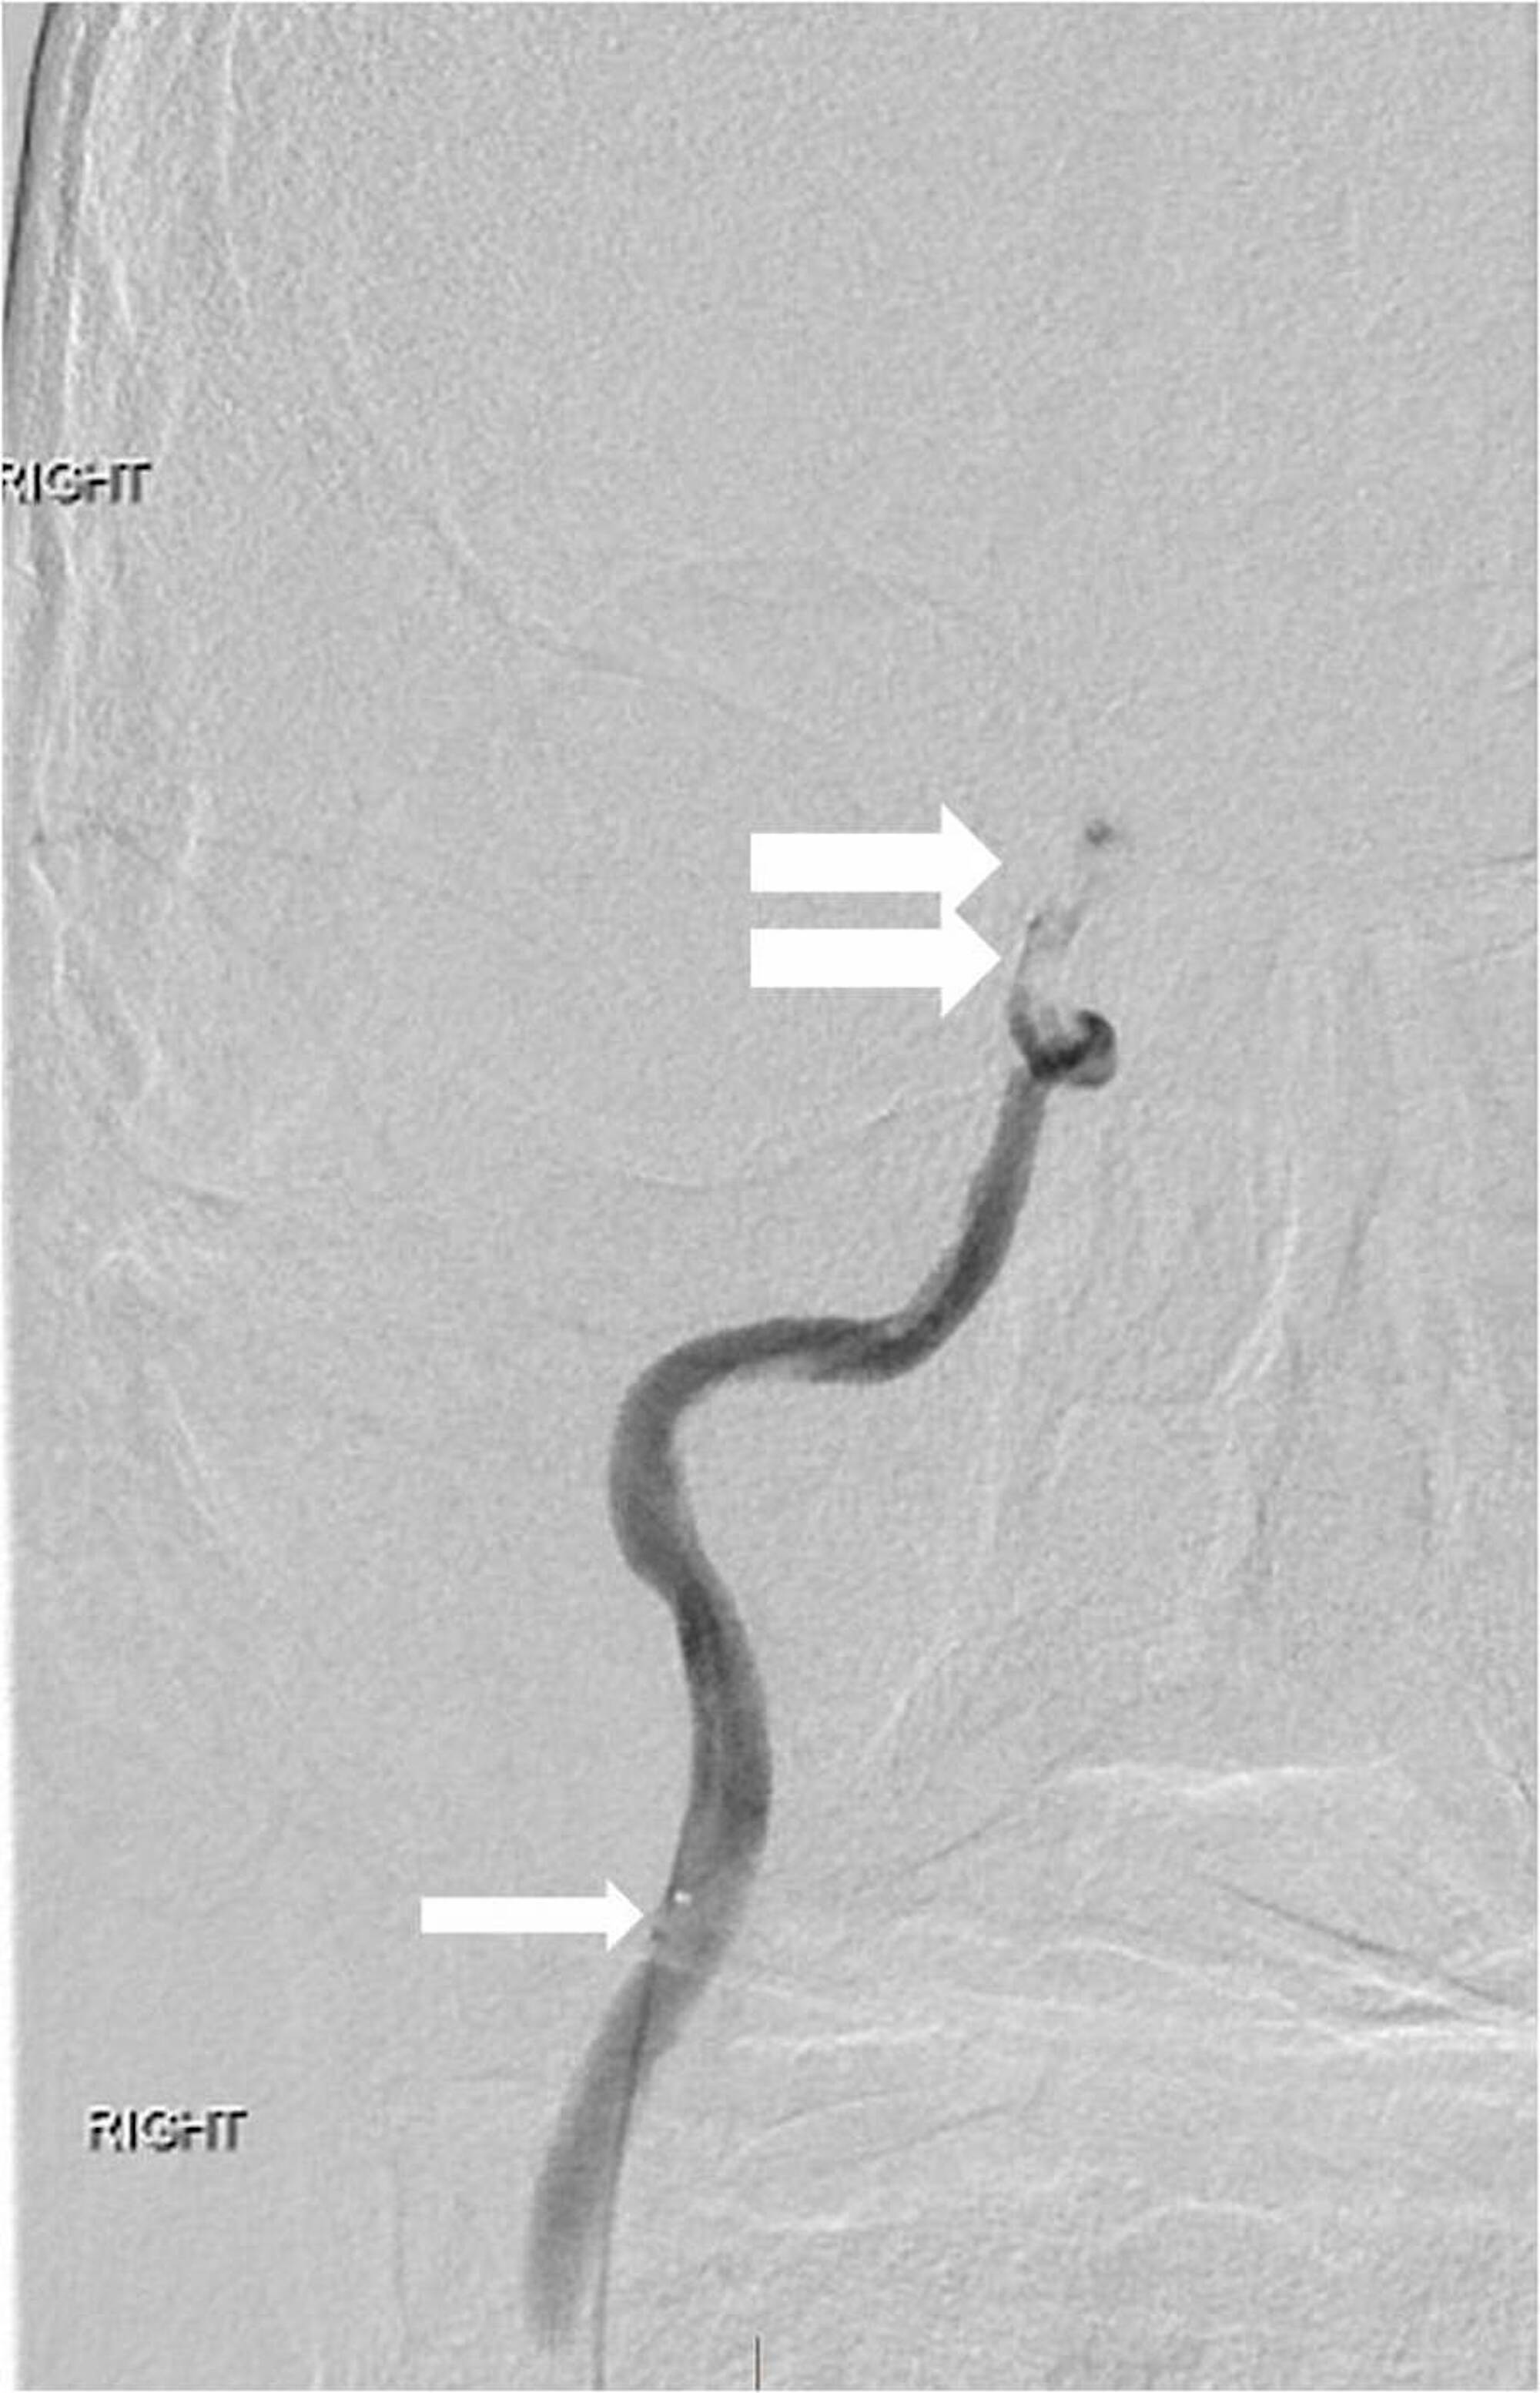

A 63-year-old man with a history of hypertension, hyperlipidemia, peripheral artery disease, smoking, and Stage IV lung cancer presented with left-sided weakness and dysarthria when he visited our institution for a chemotherapy port placement. His National Institutes of Health Stroke Scale (NIHSS) score was six and he was not a candidate for intravenous (IV) thrombolytics. Computed tomography angiography (CTA) revealed occlusion of the extracranial right internal carotid artery (ICA) and right middle cerebral artery (MCA) but no hemorrhage or large areas of acute ischemic change. Biplane digital subtraction angiography (DSA) revealed tapering to occlusion of the proximal right cervical ICA at the level of the carotid artery bulb (Figure 1).